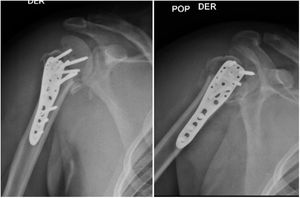

Se realizó reducción abierta de luxación escapulo humeral, osteosíntesis en húmero y reparación del manguito rotador del hombro derecho con una incisión deltopectoral de aproximadamente 20 centímetros que compromete piel y tejido celular subcutáneo; se realiza hemostasia del sangrado a nivel de capas, se hace una disección roma del músculo deltoideo dónde se pudo observar una fractura multifragmentaria de la cabeza del húmero proximal con luxación de la cabeza, se realiza apertura del manguito rotador a través del intervalo de los rotadores entre el subescapular y supraespinoso, disección roma hasta llegar a la cabeza del húmero, se hace reducción abierta de la luxación de la cabeza del húmero. Se realiza reducción abierta de la fractura de humero proximal fijándola inicialmente con 2 clavos Kirschner de 2.0mm, se realiza osteosíntesis con placa de humero proximal 9x3 utilizando 7 tornillos de bloqueo de 3.5mm y 3 tornillos corticales de 3.5mm, se sutura la interface del manguito rotador con suturas Parcus con puntos cruzados, se valora con intensificador de imagen dónde se observa una buena reducción y la cabeza del húmero en posición valga favoreciendo así su fijación (figs. 2 y 3).

Fue inmovilizado con cabestrillo durante el primer mes. Inició fisioterapia al mes siguiente de su intervención quirúrgica trabajando manejo del dolor y edema, recuperación de la movilidad articular, fuerza de la extremidad y actividades básicas cotidianas, el paciente solo logró realizar 20 sesiones de fisioterapia. Cada mes se realizó rayos x de control (fig. 4) con evaluación por parte de ortopedia mostrando buena evolución. A los 6 meses post quirúrgico el paciente muestra evolución satisfactoria (figs. 5 y 6). Dolor leve a las rotaciones clasificado en 1 según escala análogo del dolor, movilidad articular: eleva hombro a 140°, abducción de 115°, rotación externa 20° rotación interna hasta T12. Consolidación de la fractura satisfactoria sin déficit neurovascular, con una puntuación en cuestionario DASH de 1.6